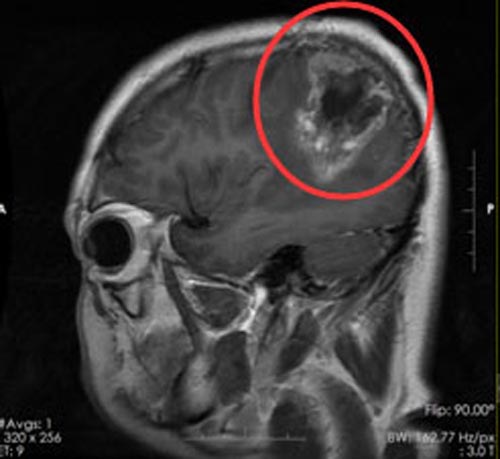

胶质瘤是一种原发性脑肿瘤,被认为起源于神经胶质干细胞或祖细胞。根据其组织学外观,传统上将其分为星形细胞瘤、少突胶质细胞瘤或室管膜瘤,并将其划分为WHO I-IV级,以此表示不同的恶性程度。

但是不管对于哪种程度的胶质瘤,手术一直以来都是优选的治疗手段,但是由于胶质瘤位于颅内,神经血管密布,可能会出现肿瘤无法完全切除的情况。而质子治疗的出现,成了存在手术残余的胶质瘤患者的辅助治疗手段。质子治疗是使用医用加速器产生的高能质子束,以较高的速度射入人体。质子束在进入人体后,大部分能量沉积在射程末端,形成尖锐的剂量峰,称为Bragg峰。通过调整,可以使Bragg峰在特定深度、准确覆盖整个肿瘤靶区,并将全部能量释放到癌变部位,准确杀伤肿瘤而不损伤周边的正常组织,从而达到良好的治疗效果。